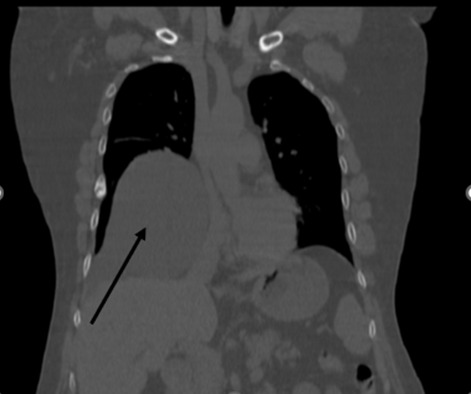

Предоперационные лабораторные исследования не показали каких-либо отклонений от нормы. Информативными были инструментальные исследования. На аксиальных КТ- изображениях грудной клетки и реконструкциях легких в нативном режиме от 07.10.2024: справа в проекции S4-5-8-9 сегментов определяется овальной формы патологическое образование с четкими ровными контурами, однородной структуры, плотностью до 6 ед.Х., размером 19.5х10.5 см.

Рисунок 2. КТ грудной клетки во фронтальной проекции (киста перикарда указана стрелкой)

Рисунок 4. КТ грудной клетки в сагиттальной проекции (киста перикарда указана стрелкой)

Легочный рисунок деформирован, усилен. ЭКГ от 17.10.2024: ритм синусовый, правильный. Частота сердечных сокращений 78 ударов в минуту. Нормальное положение электрической оси сердца, гипертрофия левого желудочка. Спирография от 18.10.2024: нарушение дыхательной функции легких рестриктивно - обструктивного типа: рестрикция - легкой степени, обструкция проксимального отдела - средней степени. ЭХО КС 17.10.2024 год - Аортосклероз. Дилатация левого предсердия. Незначительная гипертрофия левого желудочка. Диастолическая дисфункция левого желудочка по 1 типу. Эпикардиальная жировая прослойка превышает допустимое значение (8мм). УЗИ ГДЗ 17.10.2024 год - гепатомегалия. Жировой гепатоз печени S-1. Липоматозные изменения поджелудочной железы. Солидное образование брюшной полости без четкой органопренадлежности. Правосторонний гидроторакс.

В нашем случае пациент не предъявлял каких-либо жалоб, ни со стороны дыхательной системы, ни со стороны сердечно-сосудистой системы. Подозрение на кисту возникло при прохождении рутинной обзорной рентгенографии грудной клетки, что послужило отправной точкой в истории его болезни. В дальнейшем использовался золотой стандарт диагностики кист перикарда – компьютерная томография грудной клетки. Однако, даже это не позволило поставить точный диагноз, в связи с чем было произведено оперативное вмешательство с диагностической целью. Выбор пал на миниторакотомию в связи с размерами образования: 19.5х10.5 см по данным КТ. Фактический же размер образования составил 20.0х14.0 см, а объём – один литр. Оперативное вмешательство выполнено без особых технических трудностей, время операции составило – 95 минут. Интраоперационно заключительный диагноз не вызывал сомнений, а гистологическое исследование препарата подтвердило его.